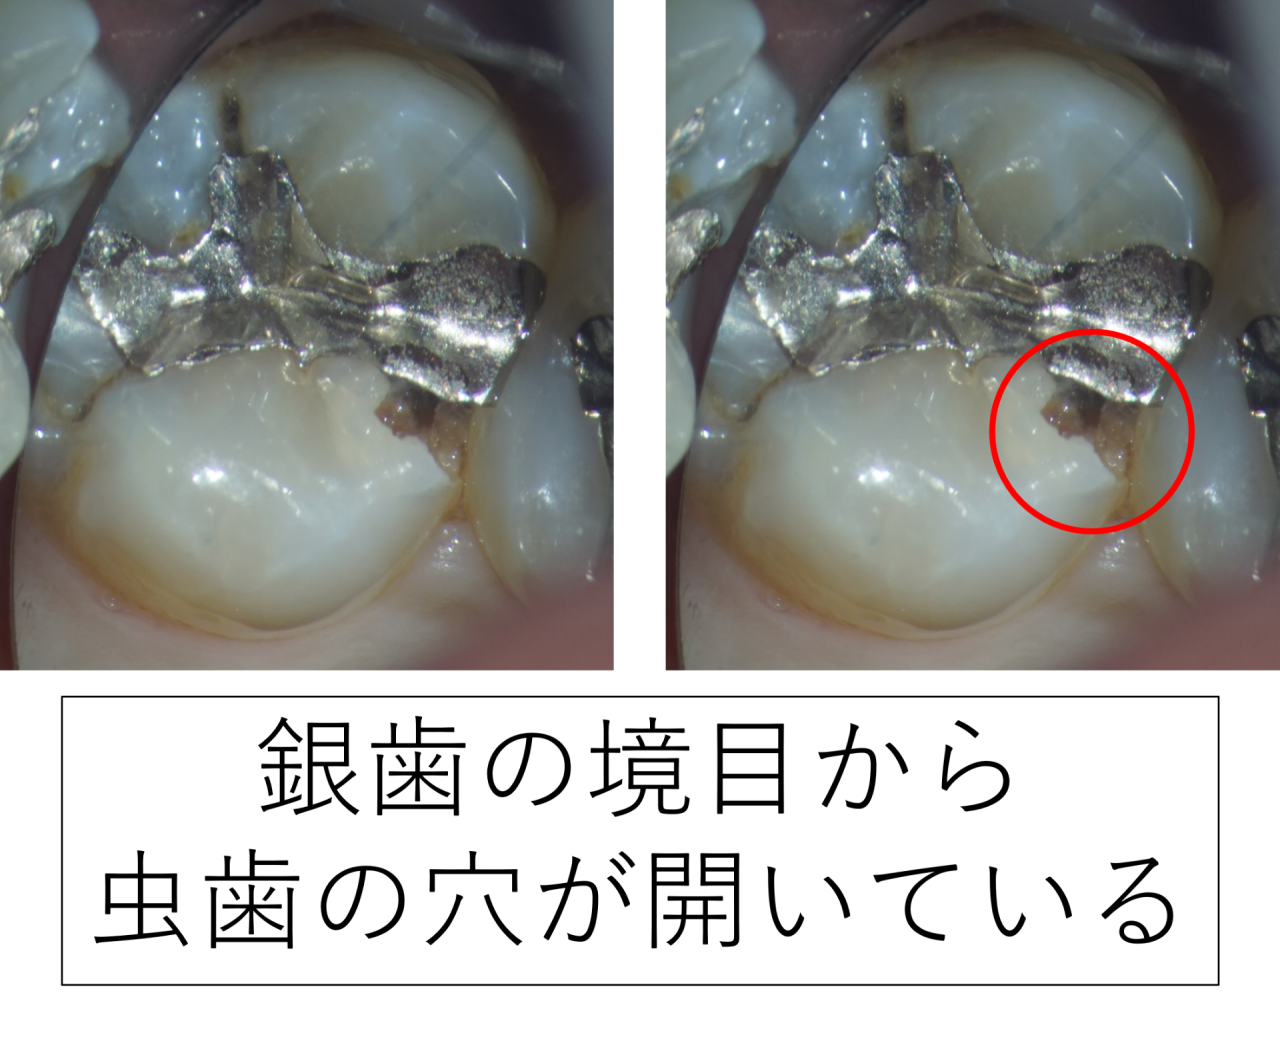

銀歯の下で虫歯が進行していた状態

最初に来院されたときの写真では、

銀歯の縁(境目)に小さな段差があり、その部分に虫歯の穴が見られました。

どちらの流れも、今回の写真と一致していました。